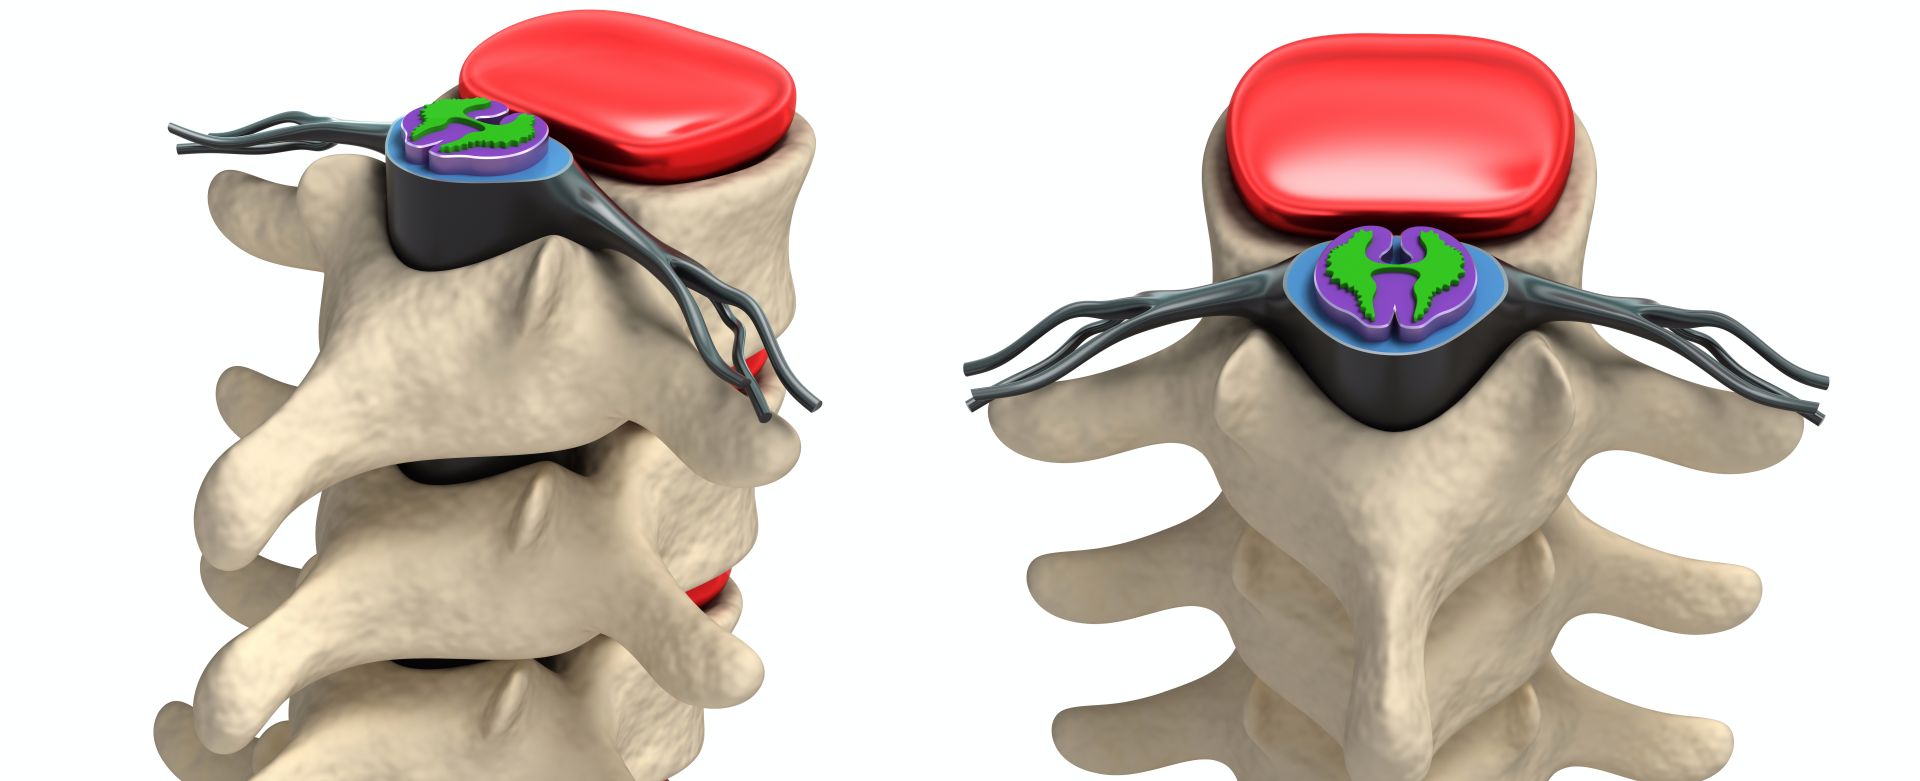

Περιγραφή της μεθόδου

Για την εφαρμογή της διέγερσης νωτιαίου μυελού, ένα ή παραπάνω ηλεκτρόδια εμφυτεύονται με τοπική αναισθησία και ακτινοσκοπική καθοδήγηση στον επισκληρίδιο χώρο, στο οπίσθιο κέρας του νωτιαίου μυελού, και σε επίπεδο το οποίο αντιστοιχεί στο δερμοτόμιο όπου παρουσιάζεται ο πόνος. Τα ηλεκτρόδια συνδέονται μέσω υποδόριας διαδρομής με εμφυτεύσιμη γεννήτρια. Η ηλεκτρική ενέργεια που παράγεται από τη γεννήτρια εφαρμόζεται μέσω των ηλεκτροδίων στις κατάλληλες περιοχές του νωτιαίου μυελού.